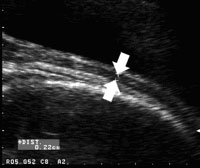

1) TRANS-ABDOMINALLY ON FULL BLADDER :

Measured at 36-38 weeks.

The arrows indicate where the LUS thickness is measured ---- the thinnest zone of the lower segment was identified visually at the midsagittal plane along the cervical canal. This area was magnified and the measurement was taken between the urinary bladder wall�myometrium interface and the myometrium/chorioamniotic membrane� amniotic fluid interface.